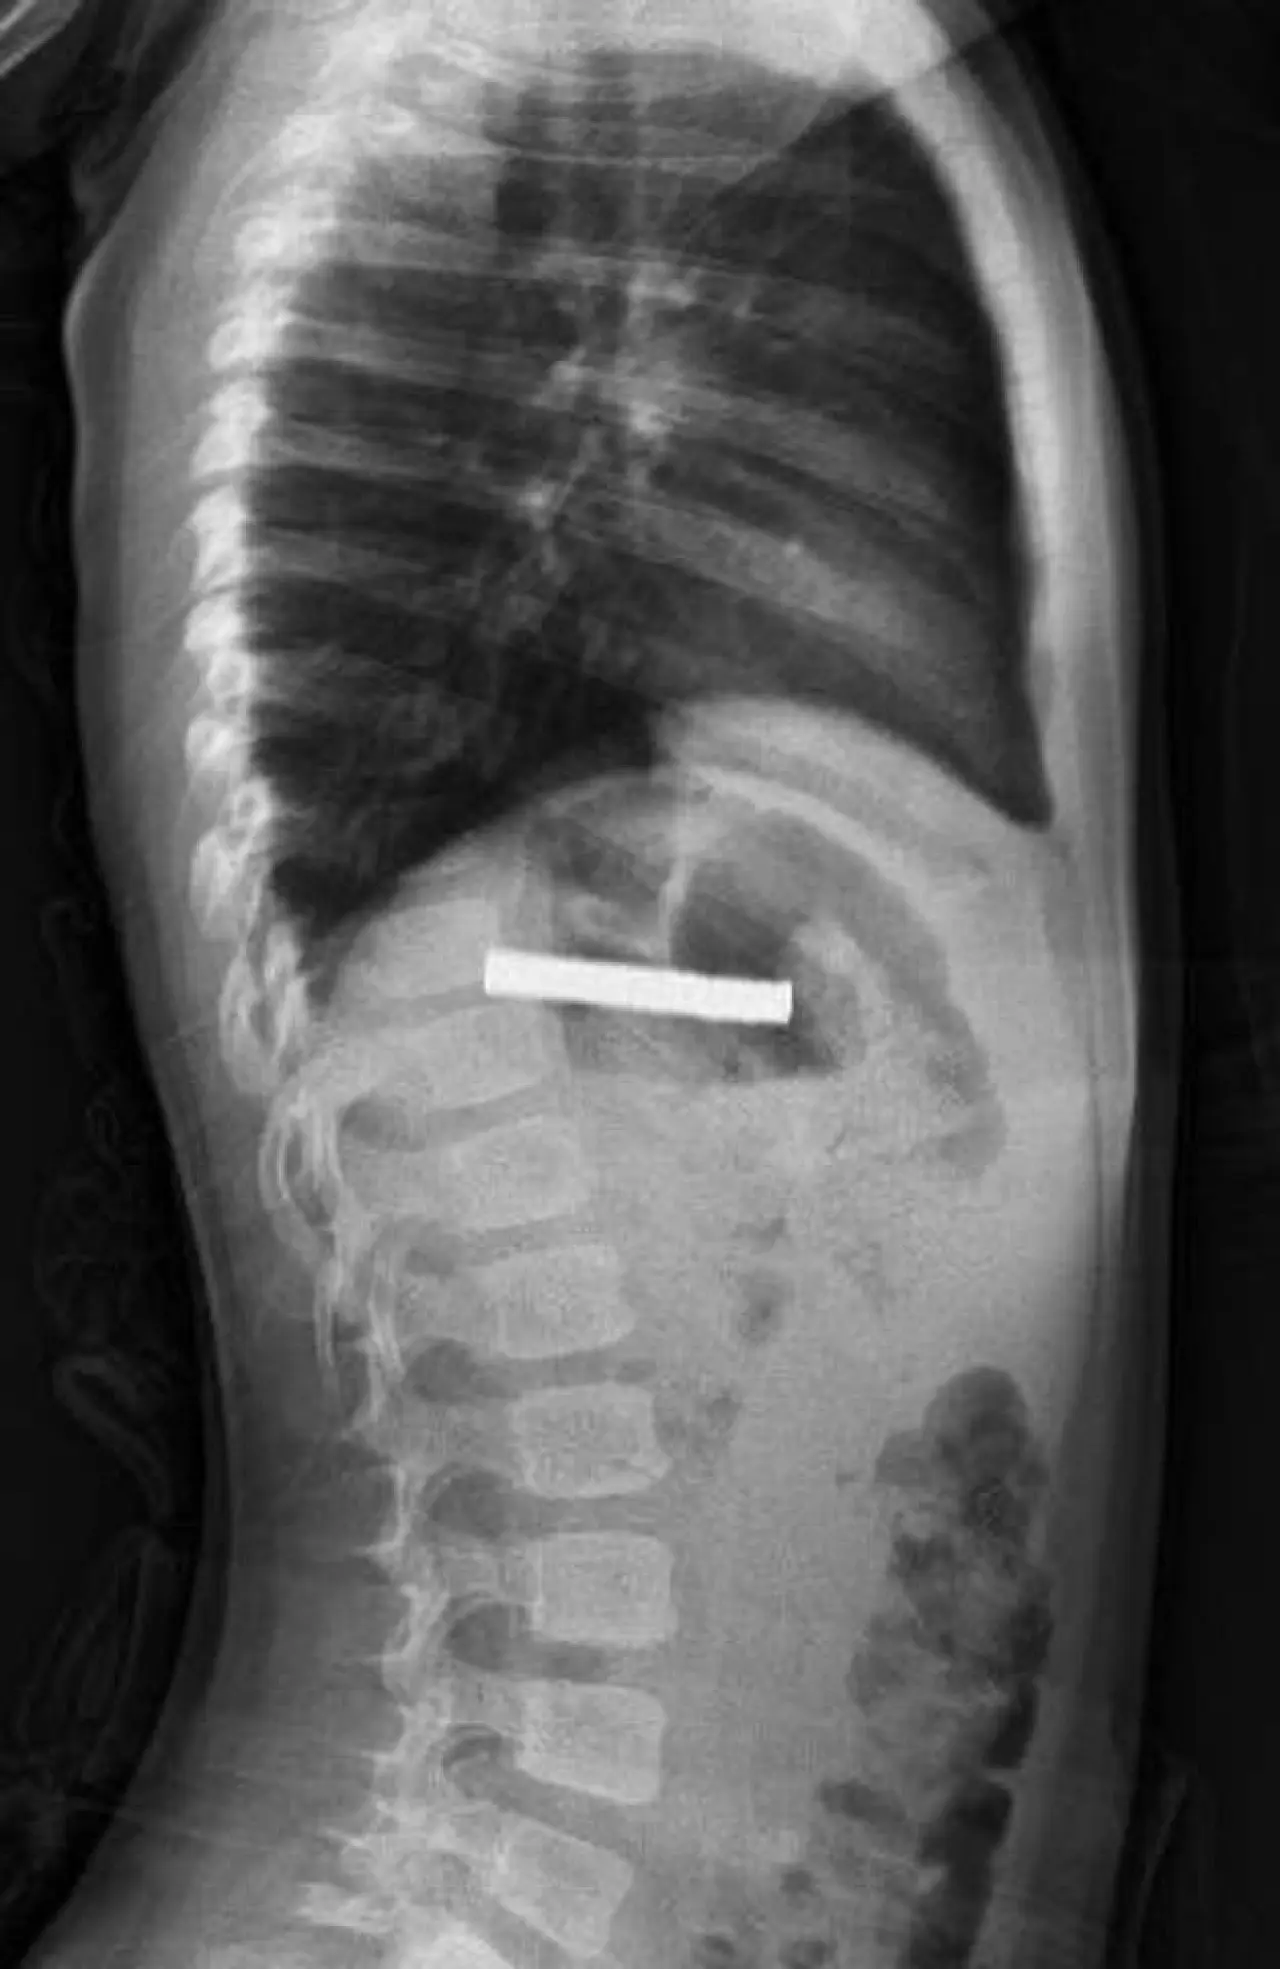

Erzurum’da bir çocuk evde bulunan 19 tane mıknatısı yuttu.

Fırat Üniversitesi Çocuk Gastroenteroloji Hepatoloji ve Beslenme Bilim Dalı Başkanı Prof. Dr. Yaşar Doğan, çocuk hastanın yemek borusuna yapışmış 19 mıknatısı endoskopik yöntemle çıkardı.

Mıknatıslar uzun süre yemek borusunda takılı kaldığı için yemek borusu ve mide girişinde zedelenmeler olurken, çocuğun sağlık durumunun iyi olduğu ve taburcu edildiği öğrenildi.